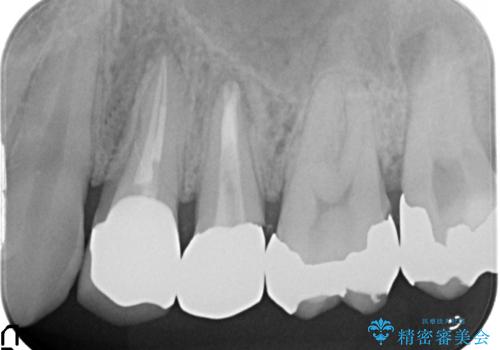

診査の結果、左上4番目の歯の神経が死んでおり、根尖に膿が溜まっていることが原因とわかりました。

そのため左上4番目の歯は根管治療を行い、歯茎の膿の出口の消失を確認後、オールセラミッククラウンによる補綴を行いました。

今回用いたオールセラミッククラウンはジルコニアフレームという白い素材の上にセラミックを盛っているため、審美性が非常に高いのが特徴です。

また、ジルコニアは人工ダイヤモンドの材料にも使われているほど高い強度を持っており、そのためオールセラミッククラウンは審美性だけでなく、奥歯やブリッジの補綴も可能とするクラウンです。